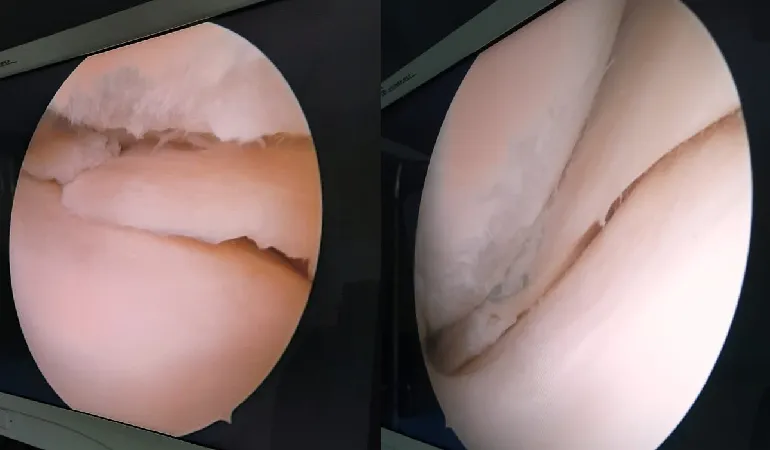

His clinical journey is defined by an extraordinary milestone of performing more than 10,000 successful surgeries. This vast experience ranges from routine fracture care to some of the most complex joint replacements and arthroscopic procedures in the region. Dr. Shah’s practice at Vedant Hospital, Gota, is built on the pillars of precision, ethical practice, and deep-rooted compassion.